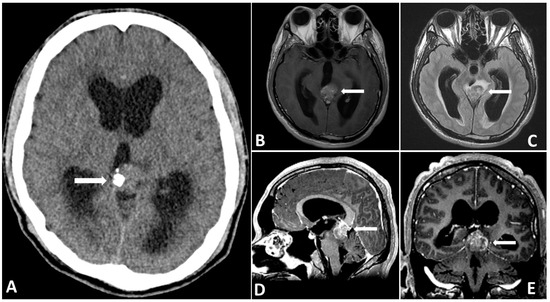

Figure 1.

Preoperative CT (A) showing a partially calcified mass in the pineal region causing hydrocephalus. Preoperative MRI showing that the (B) tumor mass is hyperintense on T2-FLAIR images. (C–E) Gadolinium-enhanced MRI, revealing a large pineal region tumor with heterogenous contrast enhancement.